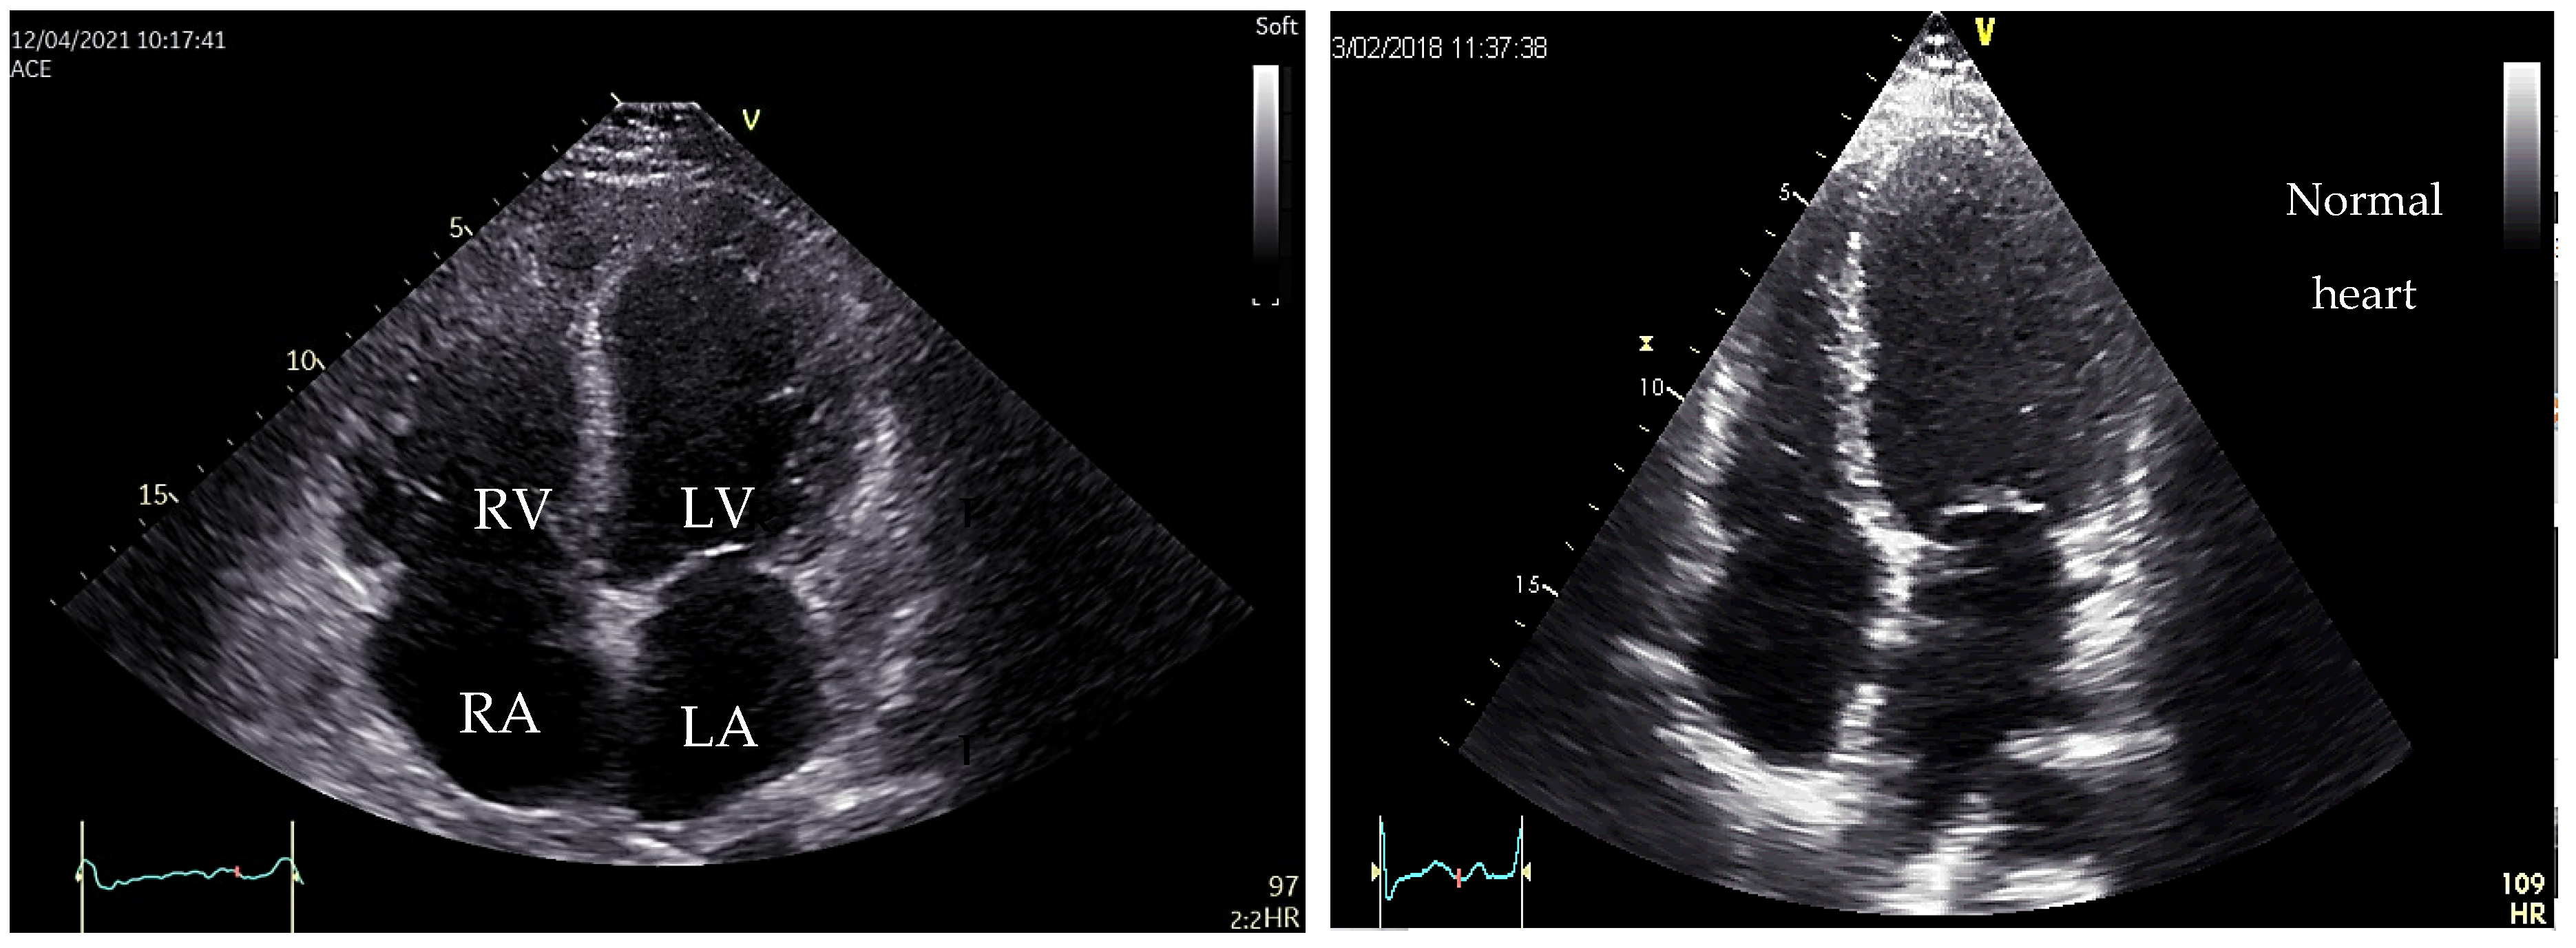

5. Dilated Cardiomyopathy (DCM)